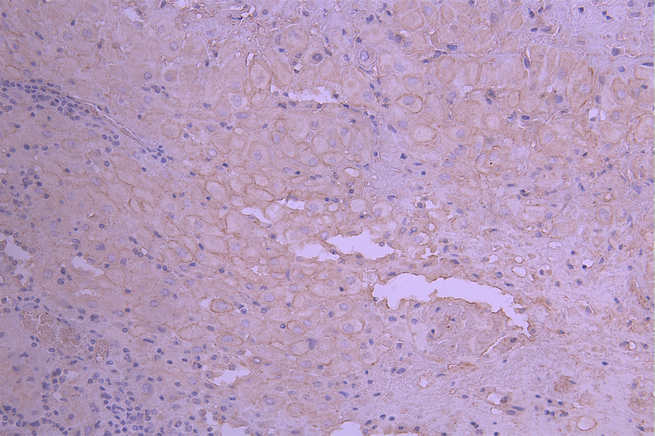

IHC image of CSB-RA014666MA1HU diluted at 1:50 and staining in paraffin-embedded human placenta tissue performed on a Leica BondTM system. After dewaxing and hydration, antigen retrieval was mediated by high pressure in a citrate buffer (pH 6.0). Section was blocked with 10% normal goat serum 30min at RT. Then primary antibody (1% BSA) was incubated at 4°C overnight. The primary is detected by a Anti-Human lgG, Fcy Fragment Specific labeled by HRP and visualized using 0.05% DAB.

IHC image of CSB-RA014666MA1HU diluted at 1:50 and staining in paraffin-embedded human prostate cancer performed on a Leica BondTM system. After dewaxing and hydration, antigen retrieval was mediated by high pressure in a citrate buffer (pH 6.0). Section was blocked with 10% normal goat serum 30min at RT. Then primary antibody (1% BSA) was incubated at 4°C overnight. The primary is detected by a Anti-Human lgG, Fcy Fragment Specific labeled by HRP and visualized using 0.05% DAB.